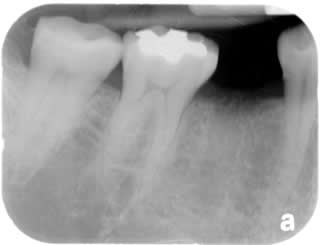

Single Tooth Implant:

Very commonly the premolars are cracked after root canal treatment.

Single tooth implant is the better choice than doing a bridge.